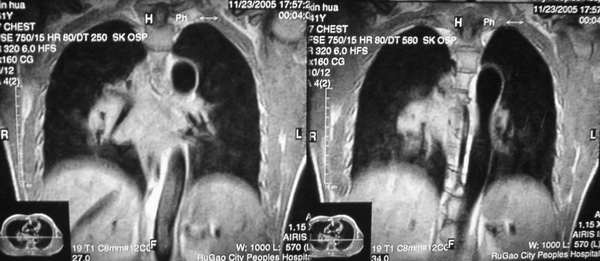

男,42岁。半年前体检发现右侧肺门肿大,mri示右侧肺门淋巴结肿大。腰背部疼痛伴右腿麻木1月入院。腹部b超示肝、胆、胰腺、脾、肾、前列腺及膀胱未见异常。afp、cea、ca199均正常。

胸部mri是半年前的,而胸部 增强ct是目前的,二者变化不大,肺部好像也没啥。

增强图像显示不清,好像有肺门及纵隔与腋下淋巴结肿大,右侧胸腔积液,腰1椎体骨质破坏,椎旁软组织肿块形成,其后硬脊膜囊明显受压。考虑淋巴瘤可能。其他待排。